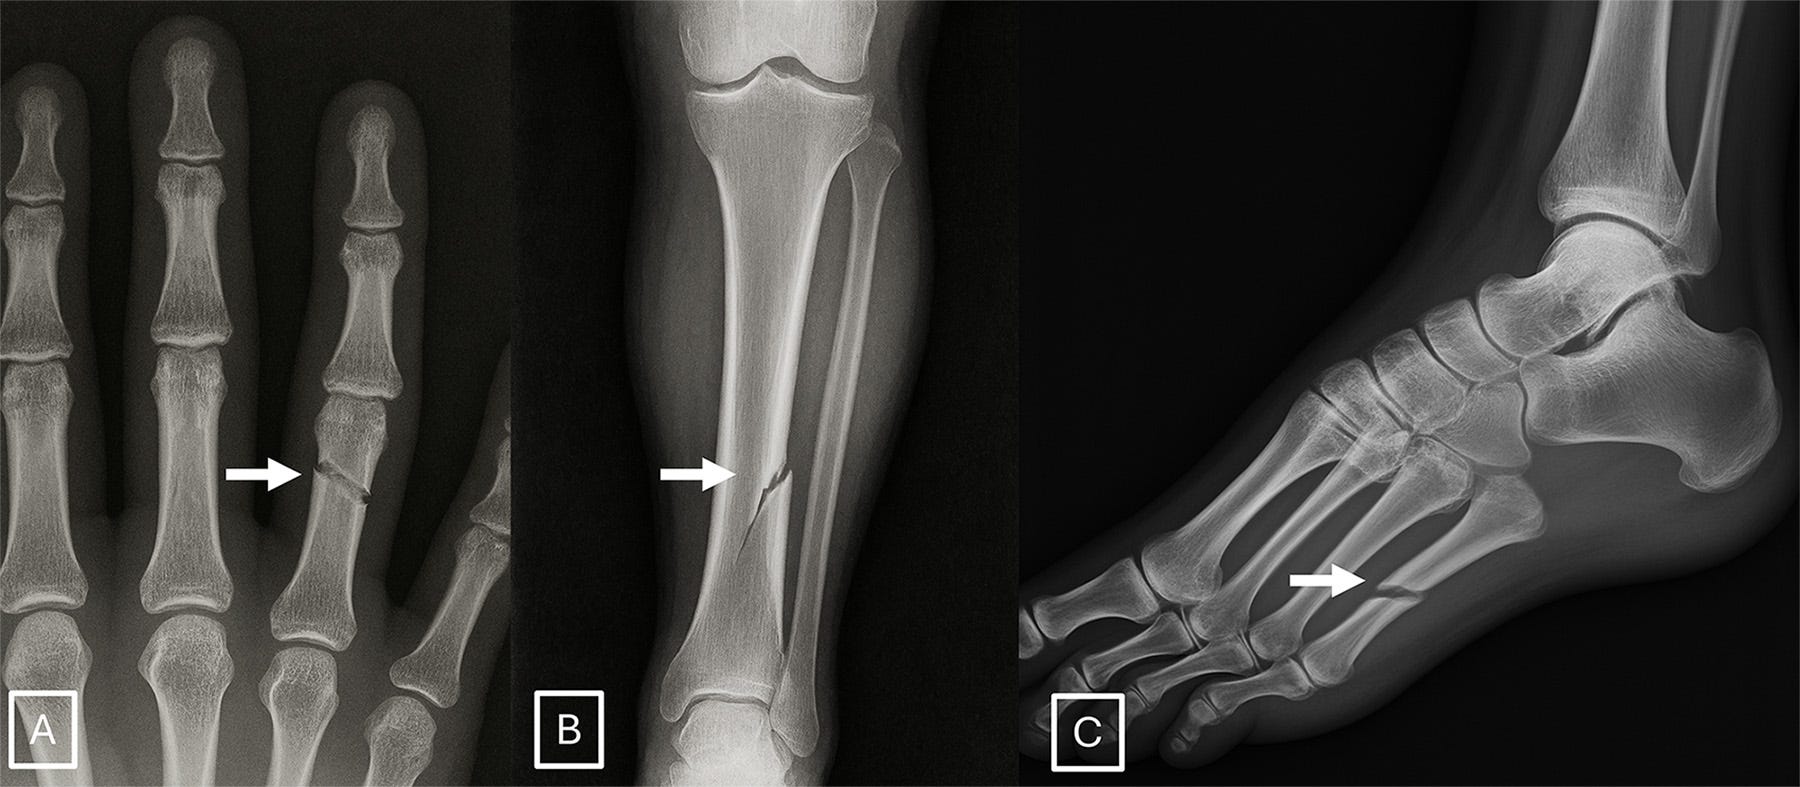

Qualitative surveying of the radiologists after the initial phases of the study indicated certain features were more suggestive of synthetic radiographs: absence of noise, overly-smooth cortex, and unnatural-appearing fracture patterns. A few examples: